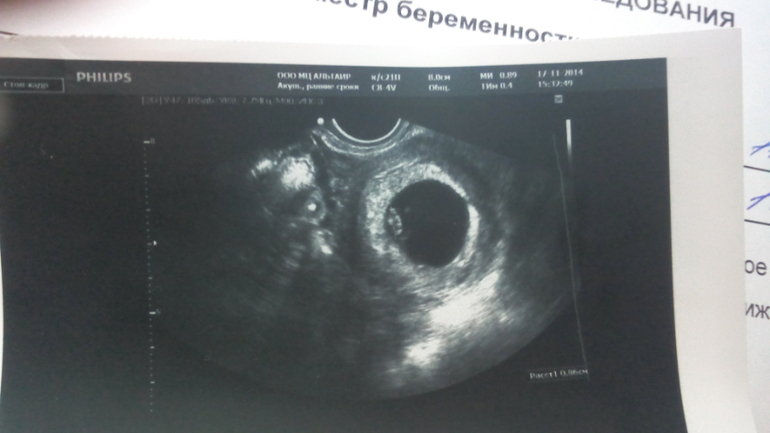

Вопросы про УЗИ, обследования и анализы: что, где, как, когда?Девочки, помогите, пожалуйста, со всем разобраться. Я, как настоящий параноик, пошла на УЗИ в 7 недель и 4 дня, но легче от этого не стало

1. Почему такой маленький КТР(или мне кажется), всего 9,9 мм, читаю, у всех девочек на моем сроке уже больше 15мм

2. ЧСС 138 ударов в минуту, норма же от 140?

И самое главное. Нет ли у меня отслойки( может быть по фотографии кто то скажет, узистка ничего не говорила вообще про это).

Диаметр желточного мешка же написан 4.3 а так вроде бы нормально. Но не знаю про ктг и чсс. Ктг у нее написано соот сроку.